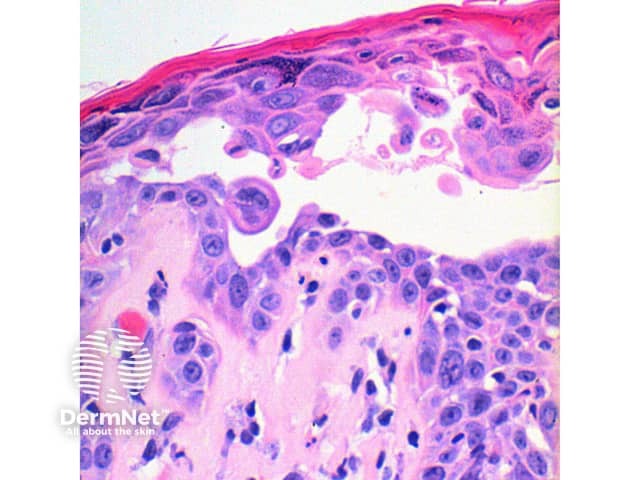

The scanning power view of the histology of Darier disease is of an epidermal and superficial dermal inflammatory process (Figure 1). Intraepidermal separation may be visible at this power, which on closer inspection is seen as suprabasal acantholysis (Figures 2 and 3). Acantholysis can be seen at all levels within the epidermis. Dyskeratosis of the keratinocytes is seen, with two notable changes described. Corps ronds refer to cells with small pyknotic nuclei, a perinuclear clear halo and eosinophilic cytoplasm (Figures 4 and 5).

Figure 3